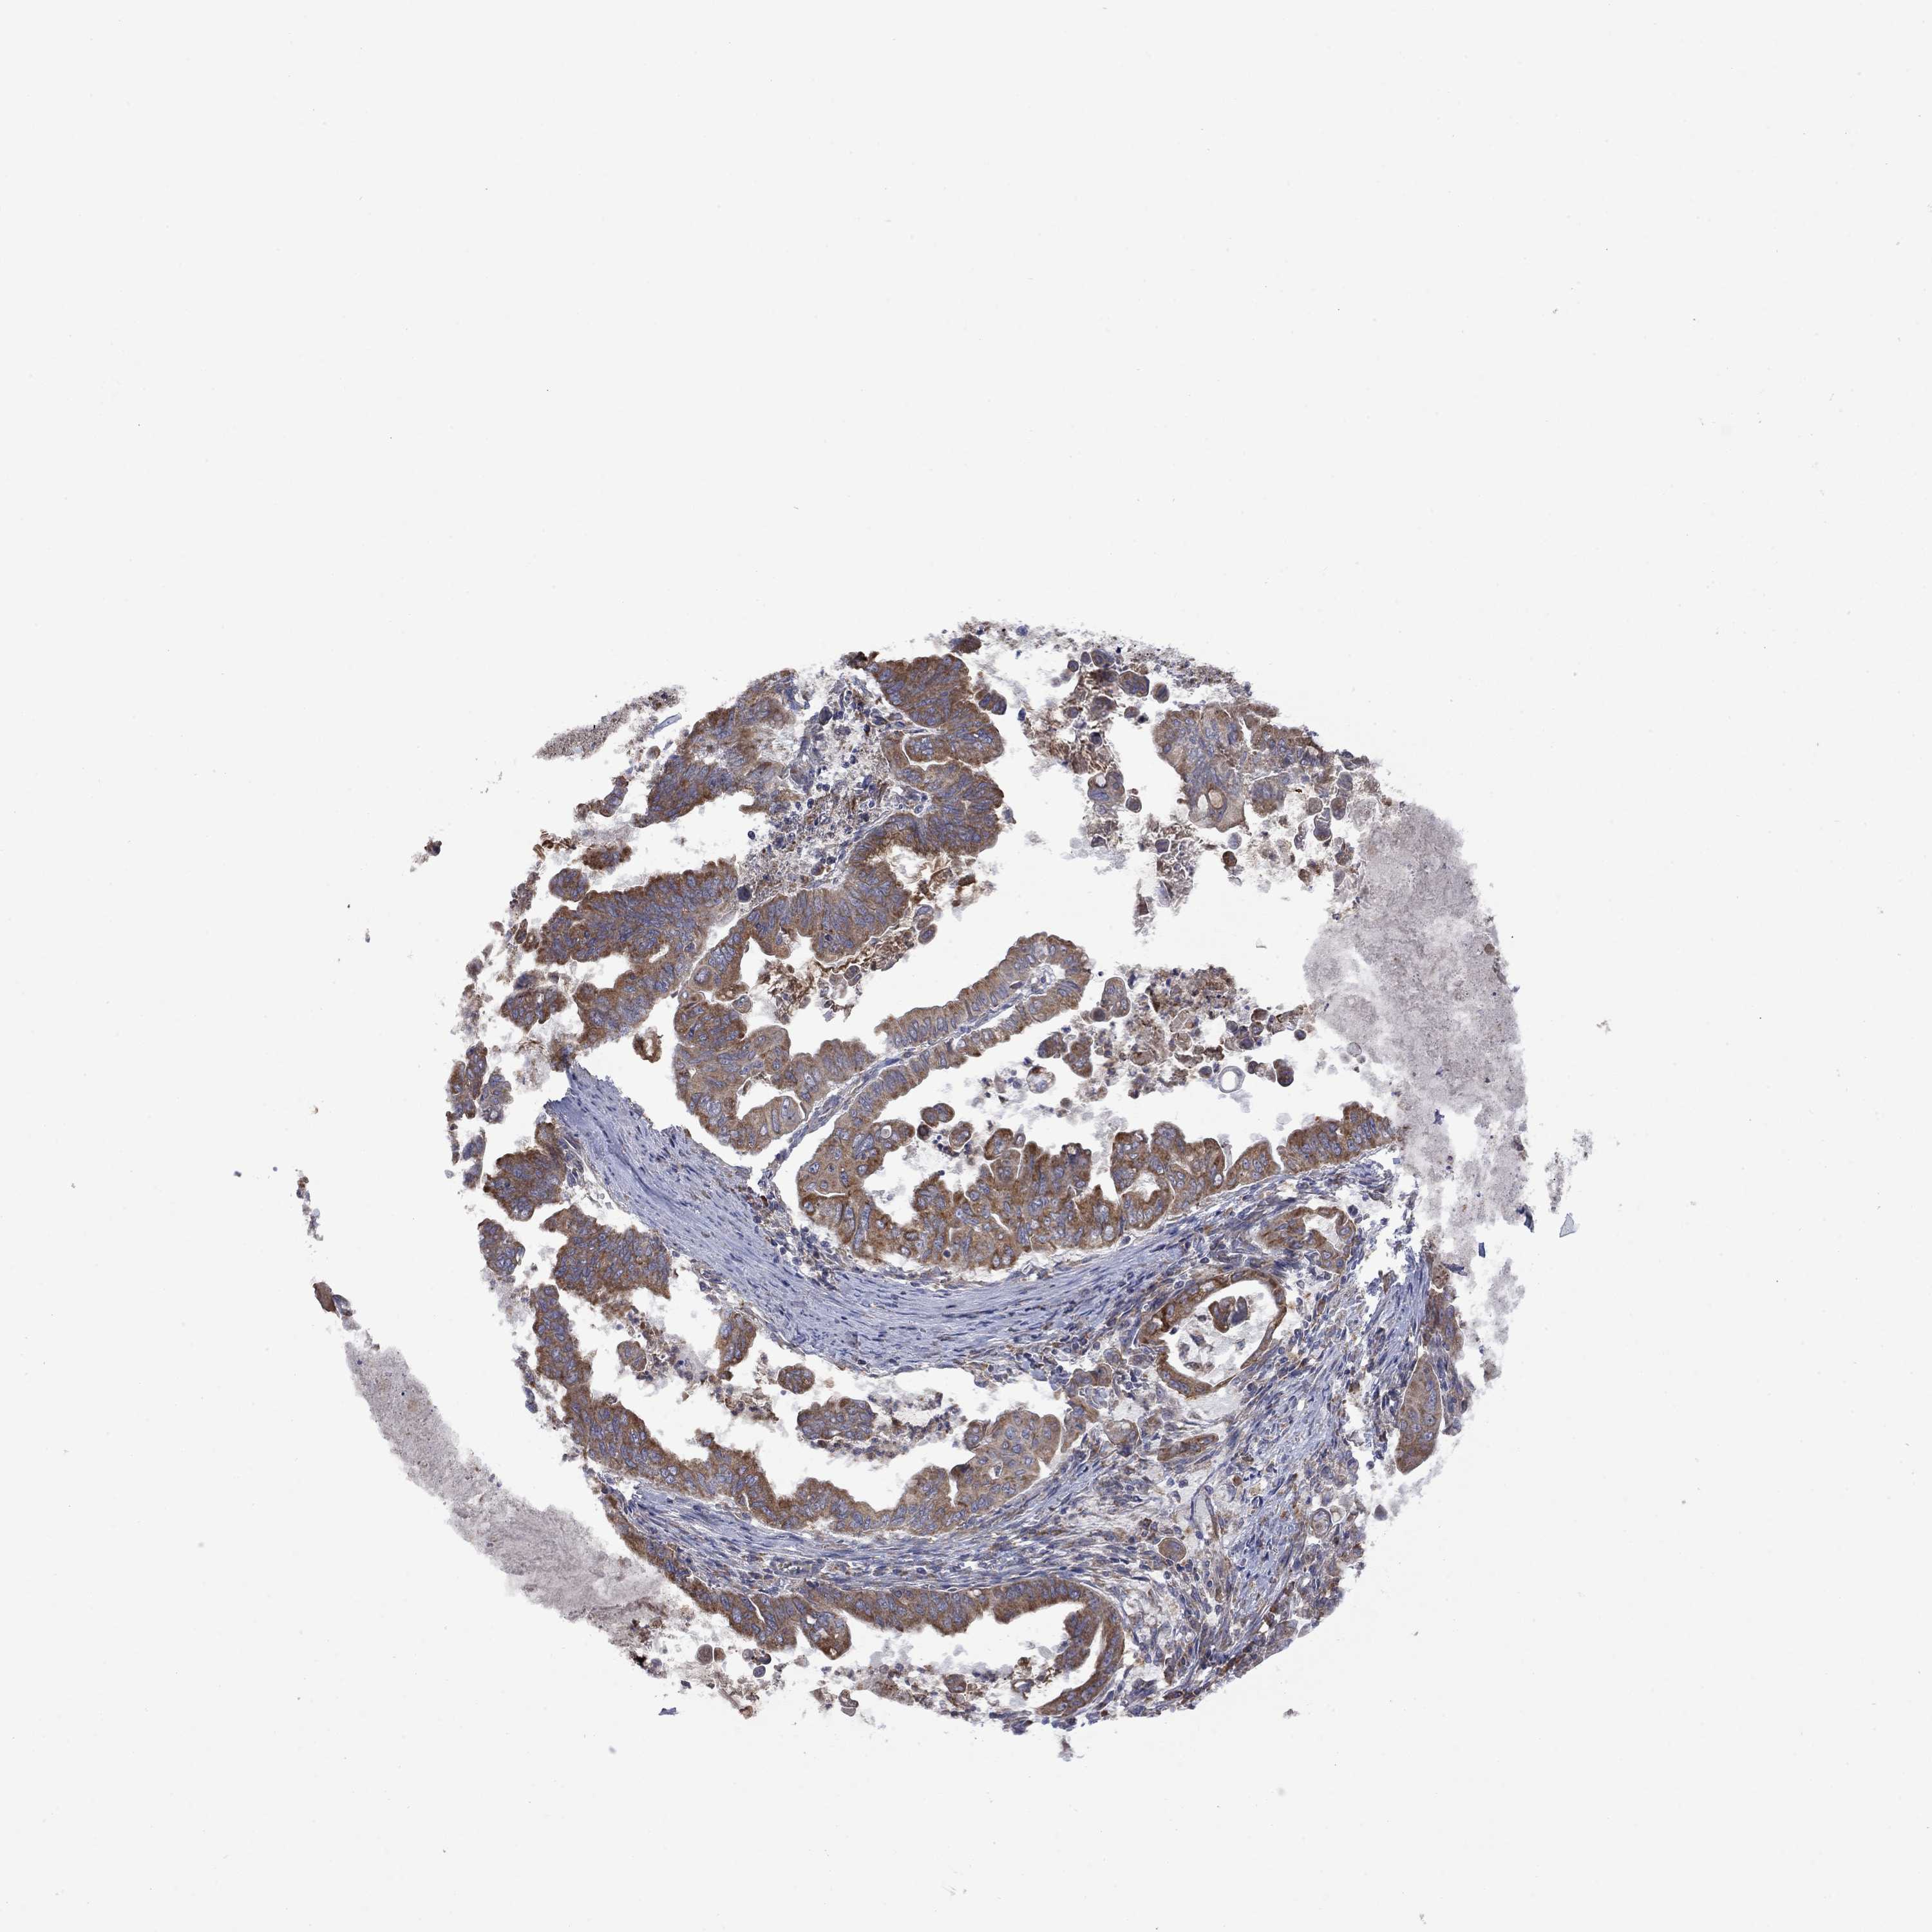

STOMACH CANCER - Protein expressioni

A mouse-over function shows sample information and annotation data. Click on an image to view it in a full screen mode. Samples can be filtered based on level of antibody staining by selecting one or several of the following categories: high, medium, low and not detected. The assay and annotation is described here.

Note that samples used for immunohistochemistry by the Human Protein Atlas do not correspond to samples in the TCGA dataset.

Antibody stainingi

Antibody staining in the annotated cell types in the current human tissue is reported as not detected, low, medium, or high, based on conventional immunohistochemistry profiling in selected tissues. This score is based on the combination of the staining intensity and fraction of stained cells.

Each image is clickable and will lead to virtual microscopy that enables deeper exploration of all samples and also displays staining intensity scores, fraction scores and subcellular localization as well as patient and tissue information for each sample.

Antibody HPA067869

Antibody CAB009499

Staining

High

Medium

Low

Not detected

Intensity

Strong

Moderate

Weak

Negative

Quantity

>75%

75%-25%

<25%

None

Location

Nuclear

Cytoplasmic/membranous

Cytoplasmic/membranous,nuclear

Adenocarcinoma, NOS

Adenocarcinoma, High grade